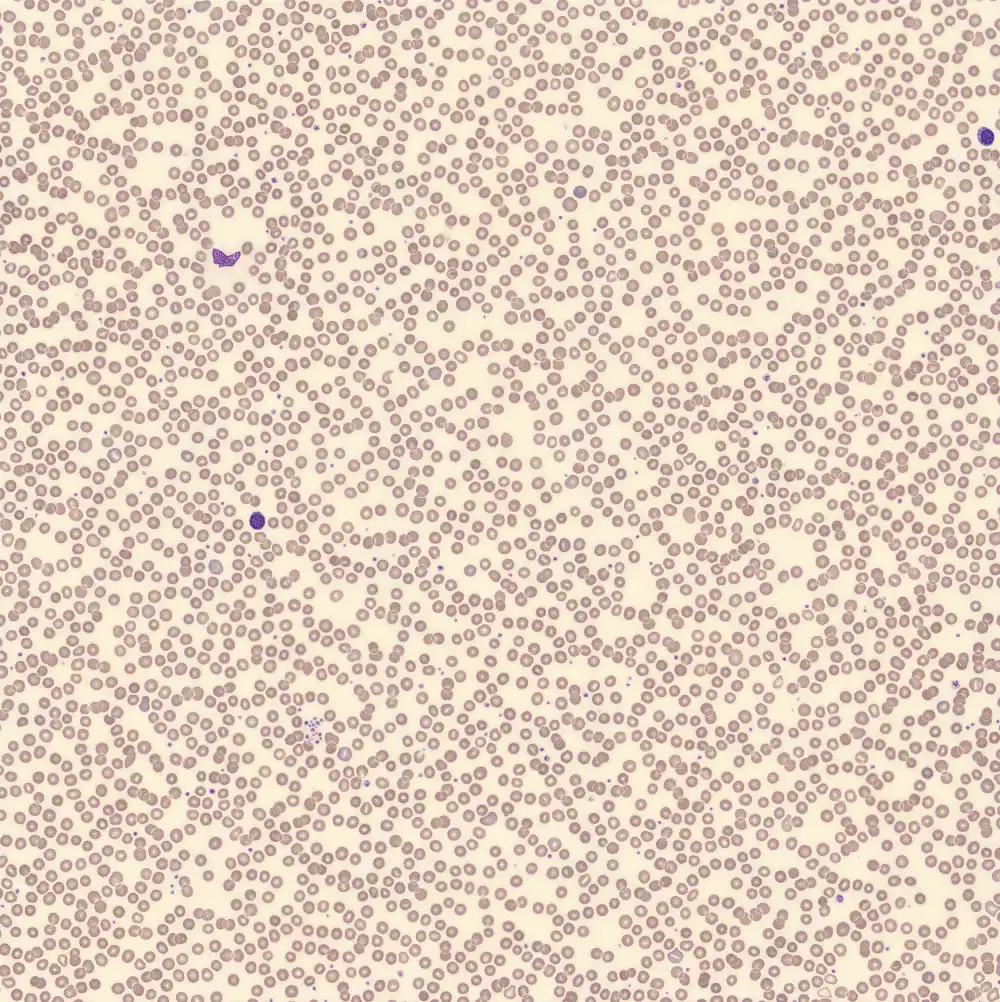

Peripheral blood

Plasma cells